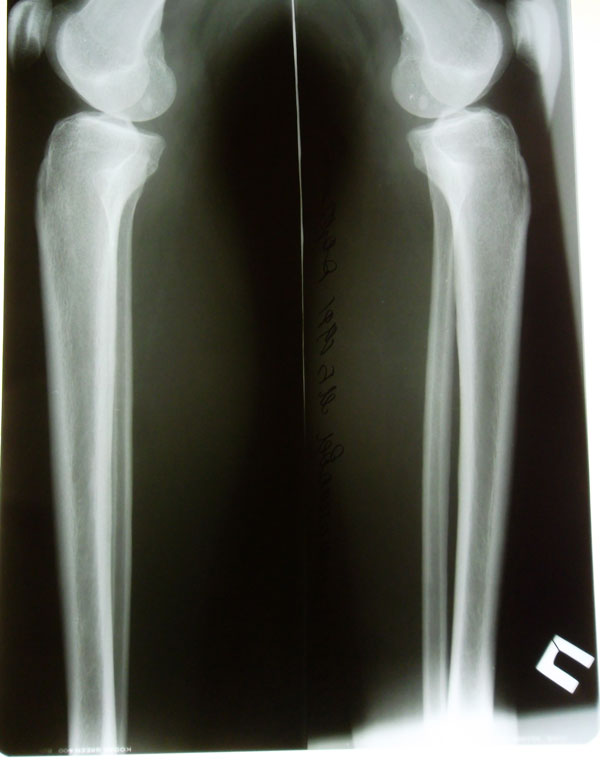

Рентгеновские снимки в прямой проекции.